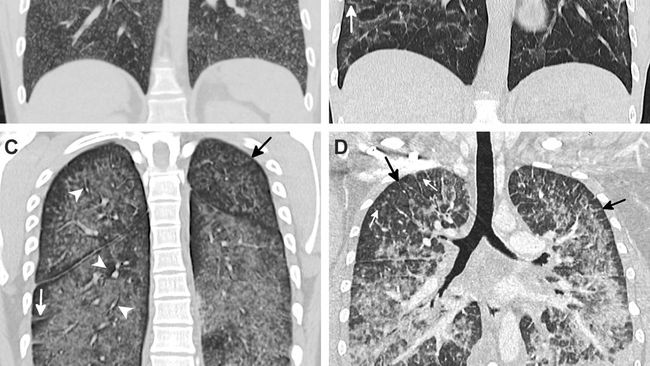

Ilustrasi Paru-paru vapers (Foto: UW Health)